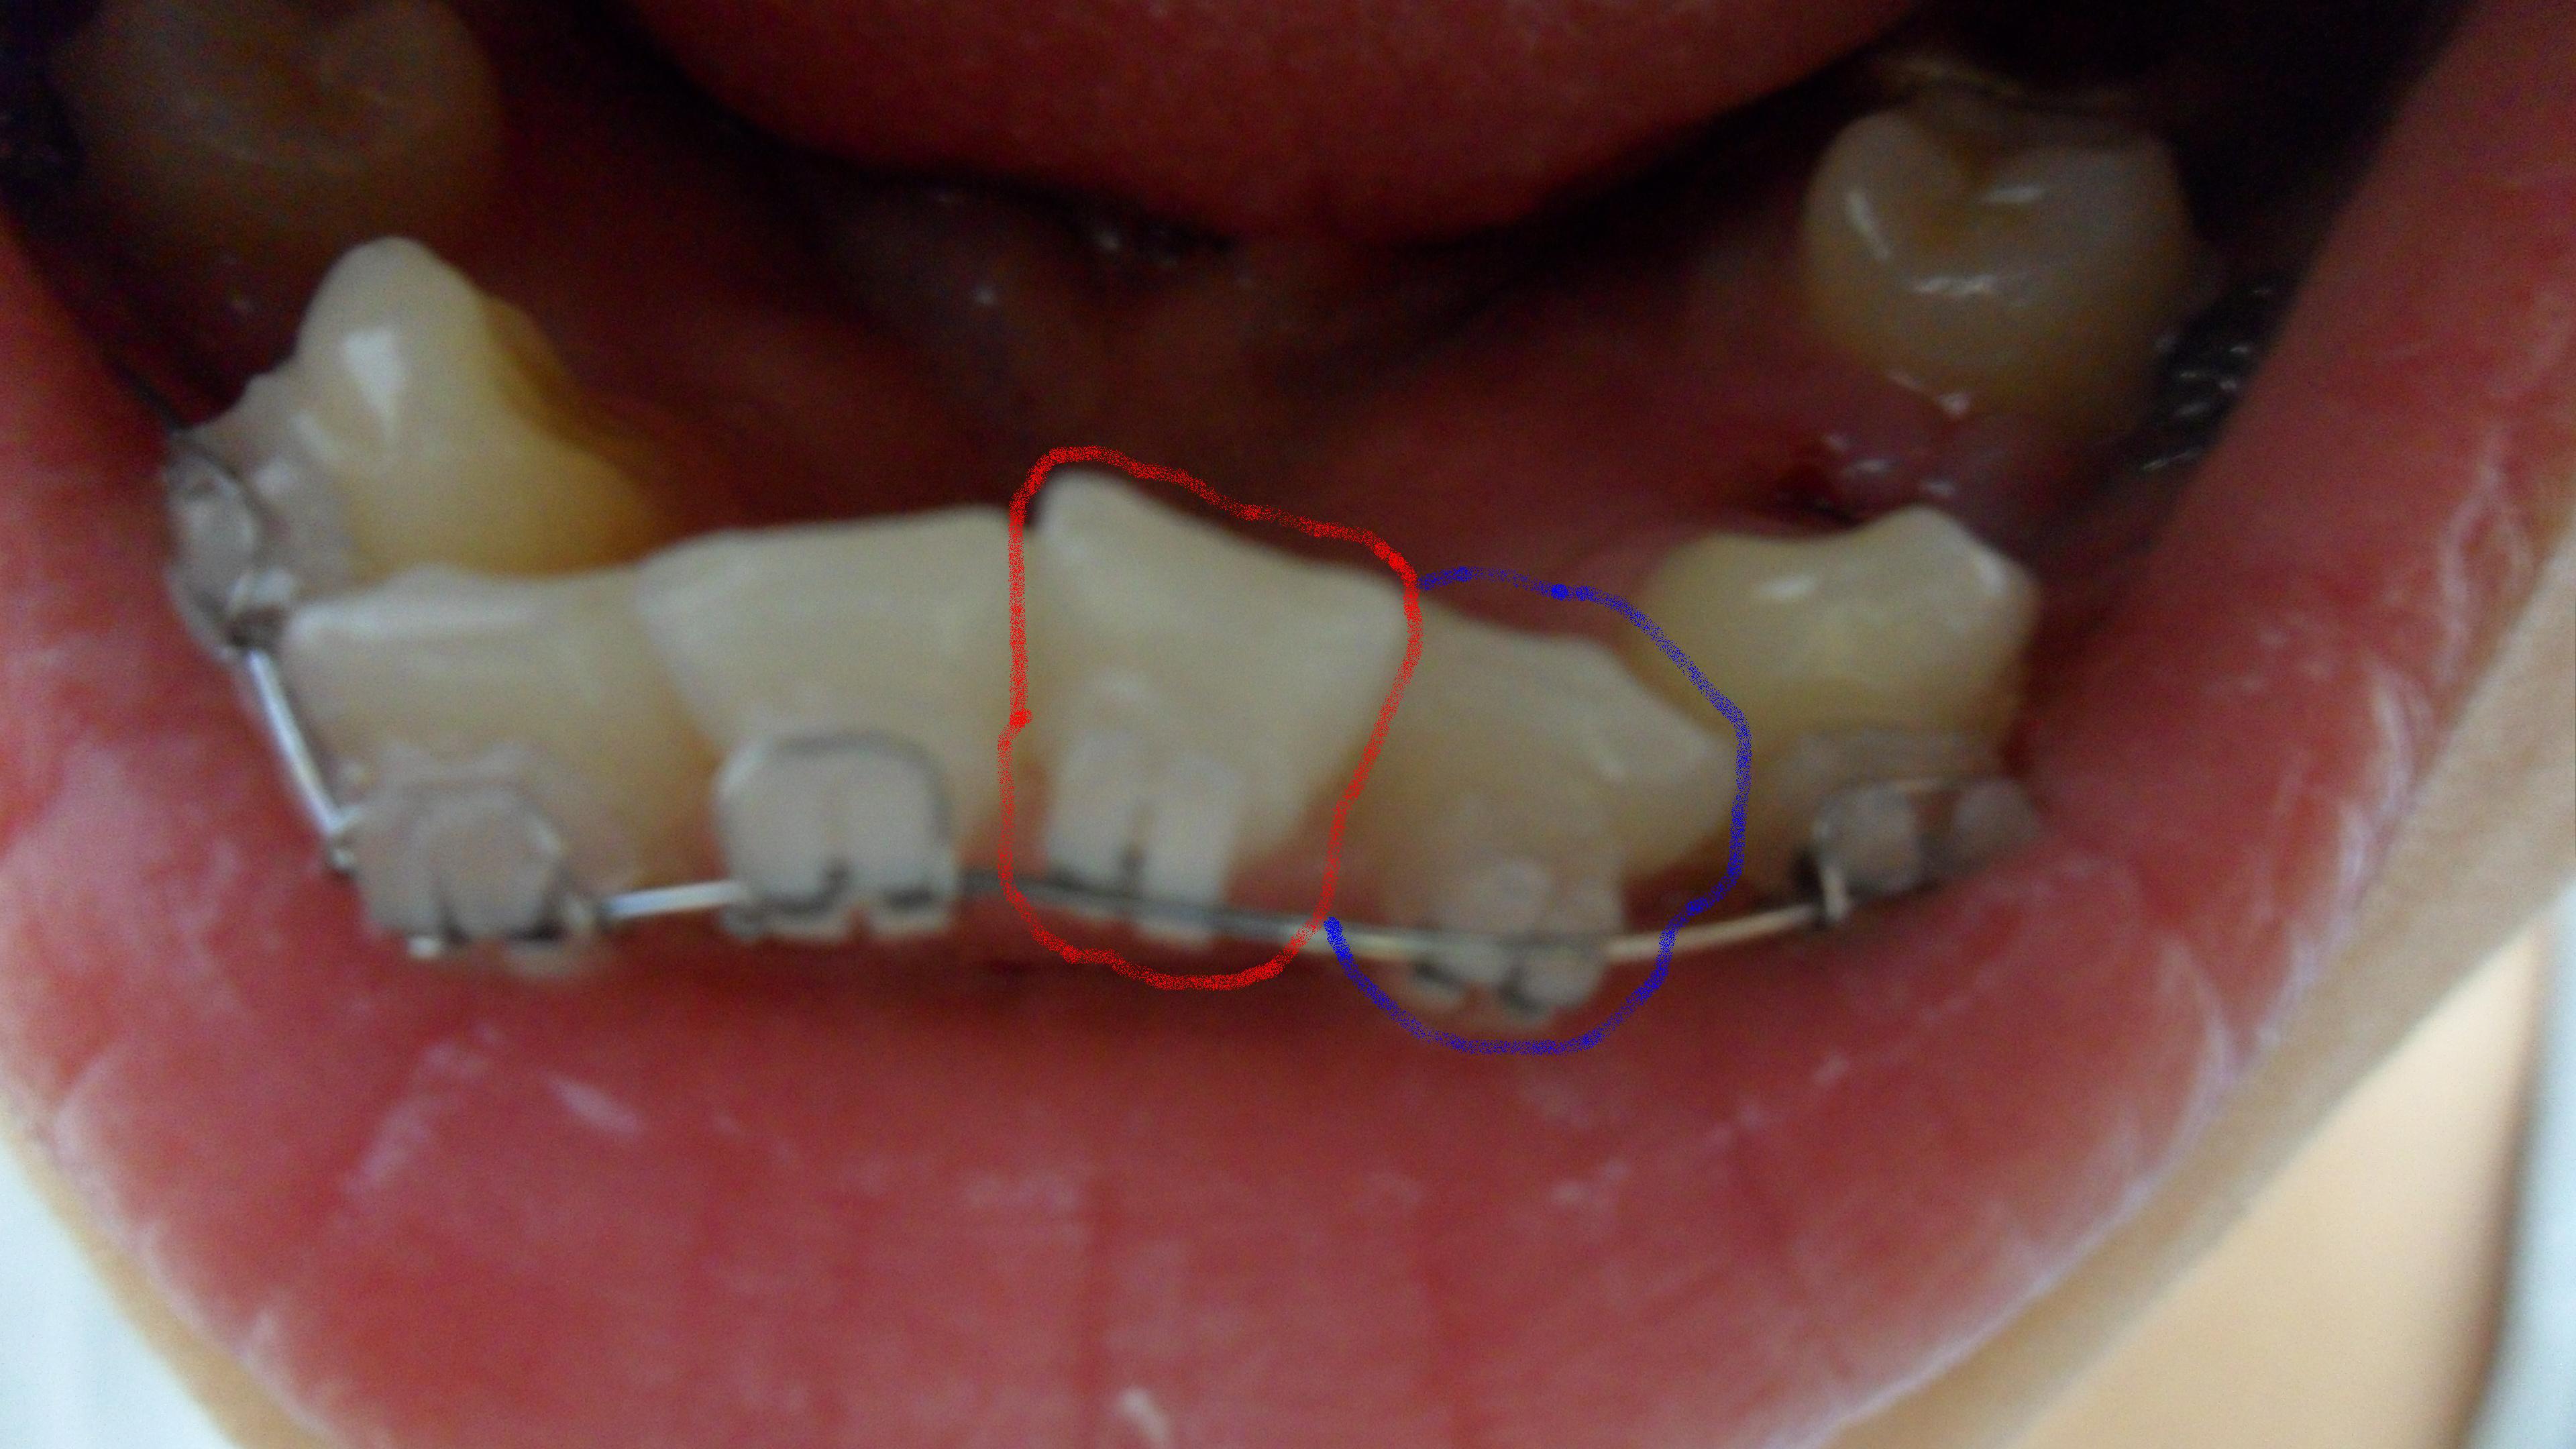

교정.....

우선 다소 혐오스러울수 있는 사진이라 죄송합니다ㅜㅜㅜ 이것이 교정전 제 치아상태입니다 제가 궁금한건 교정의 효과가 사람에 따라 미미할수도 있다고하더라구요 물론 교정전에 치과에서 찍는 사진이랑 비교하면 ...

전문의 답변 1